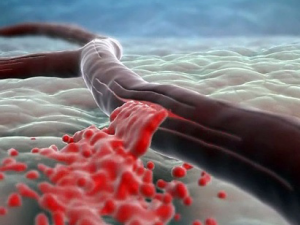

Способностью Левокарнитина стимулировать процесс образования клеток эритроцитов в кровеносной системе объясняется его назначение в период пред- и послеоперационной терапии для восполнения потерь крови из-за хирургического вмешательства.

Отметим, что эта аминокислота способствует снижению вязкости крови, что предупреждает тромбообразование.